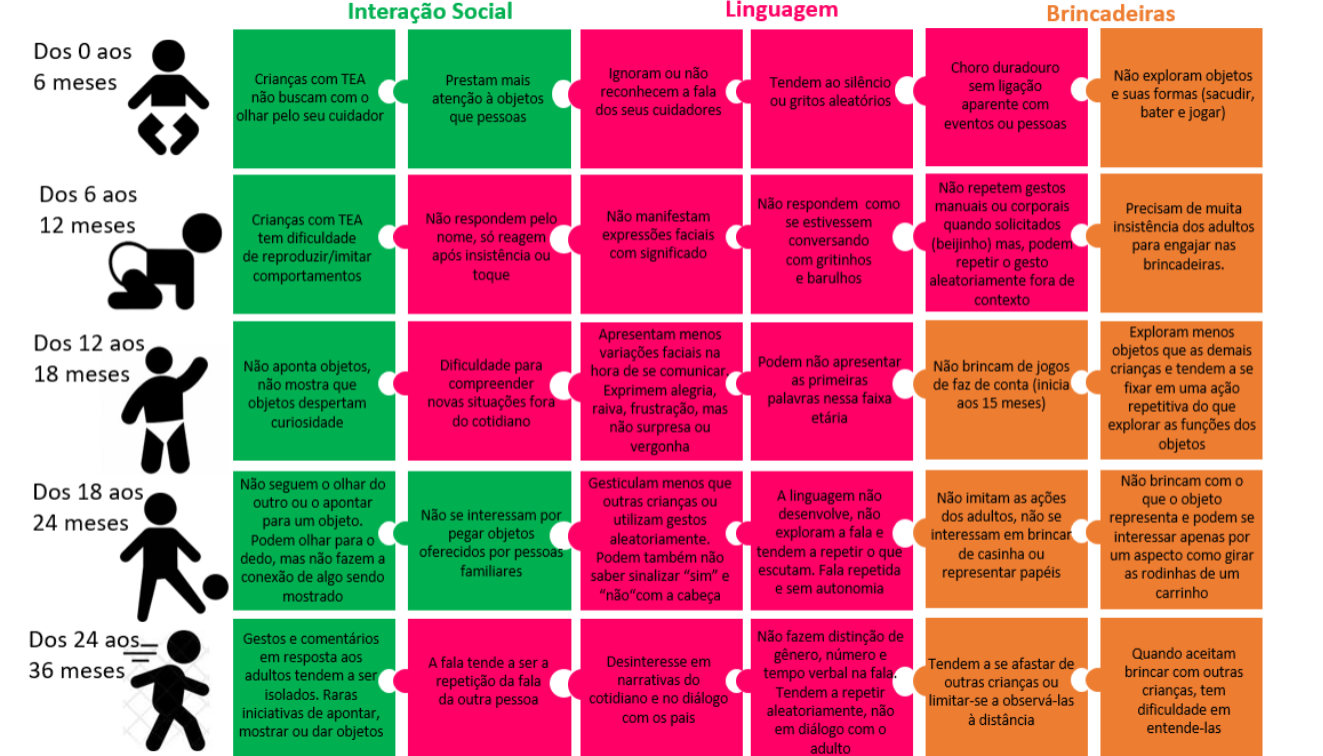

Vigilância em saúde - TEA04 abril 2025

Vigilância em saúde - TEA04 abril 2025 -